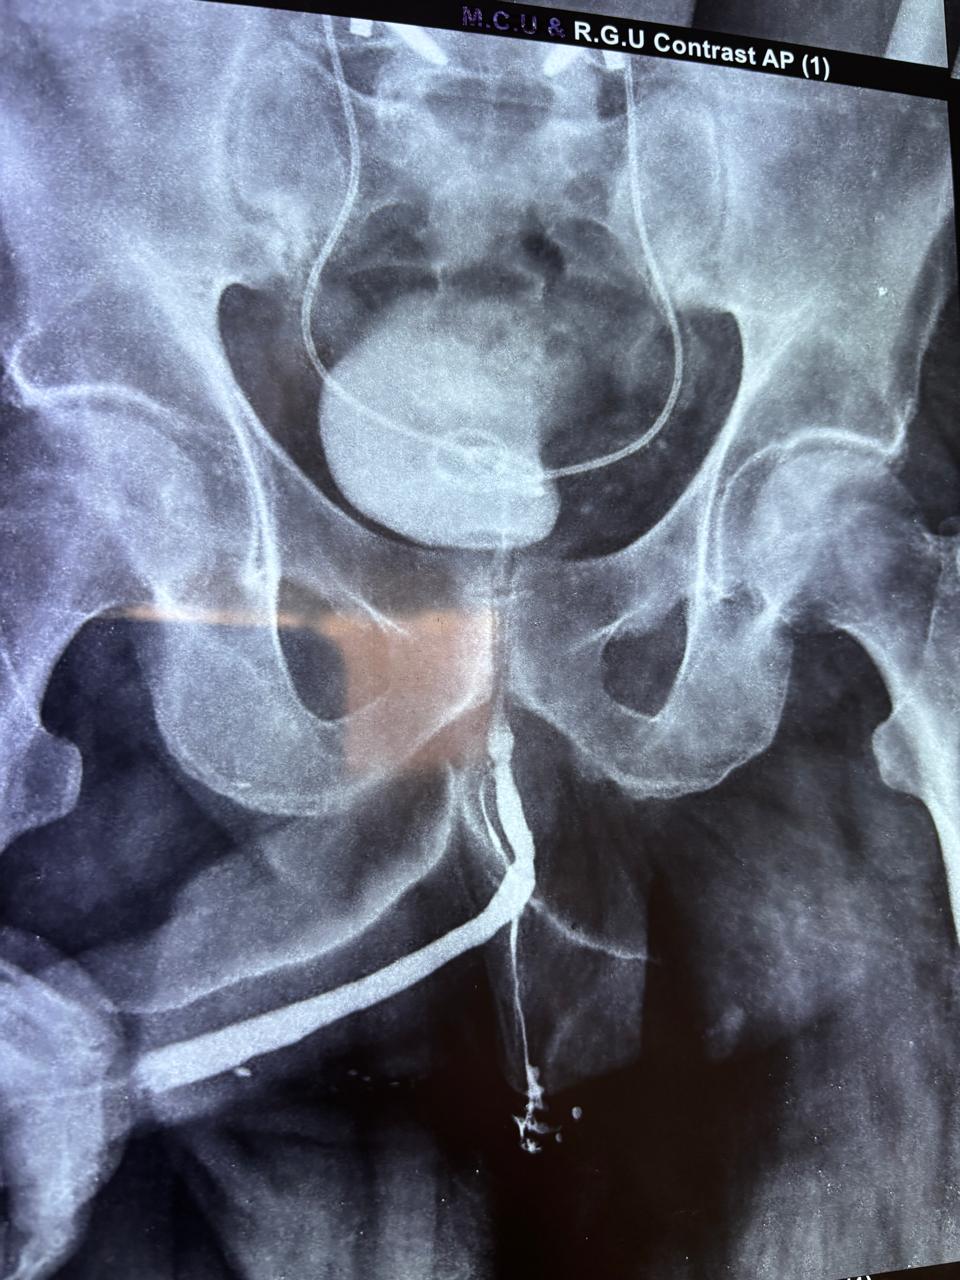

Stone Formation on Forgotten Stent

Complex Urethrocutaneous Fistula Surgery

Stricture Urethra